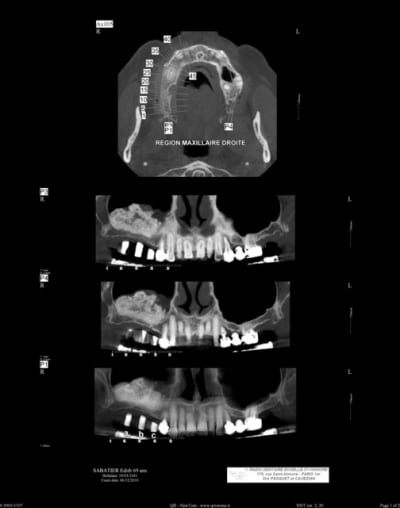

patiente ayant été implantée il y a 12 jours et toujours mal

le sinus lift a été pratiqué il y a 8 mois

les implants ont été posés sans problème, et le BM était bien dense

la cicatrisation est parfaite, pas d'oedeme, pas de déhiscence, pas de suppuration à la pression, les PC sont bien brossés, rien d'apparent à la radio de contrôle prise sous plusieurs angulations

je lui ai donné un traitement pour une sinusite (augmentin, solupred, lavage des fosses nasales), et precription d'un cone beam dans 10 jours

le sinus a été greffé il y a environ 8 mois

et les implants ont été posés il y a 15 jours